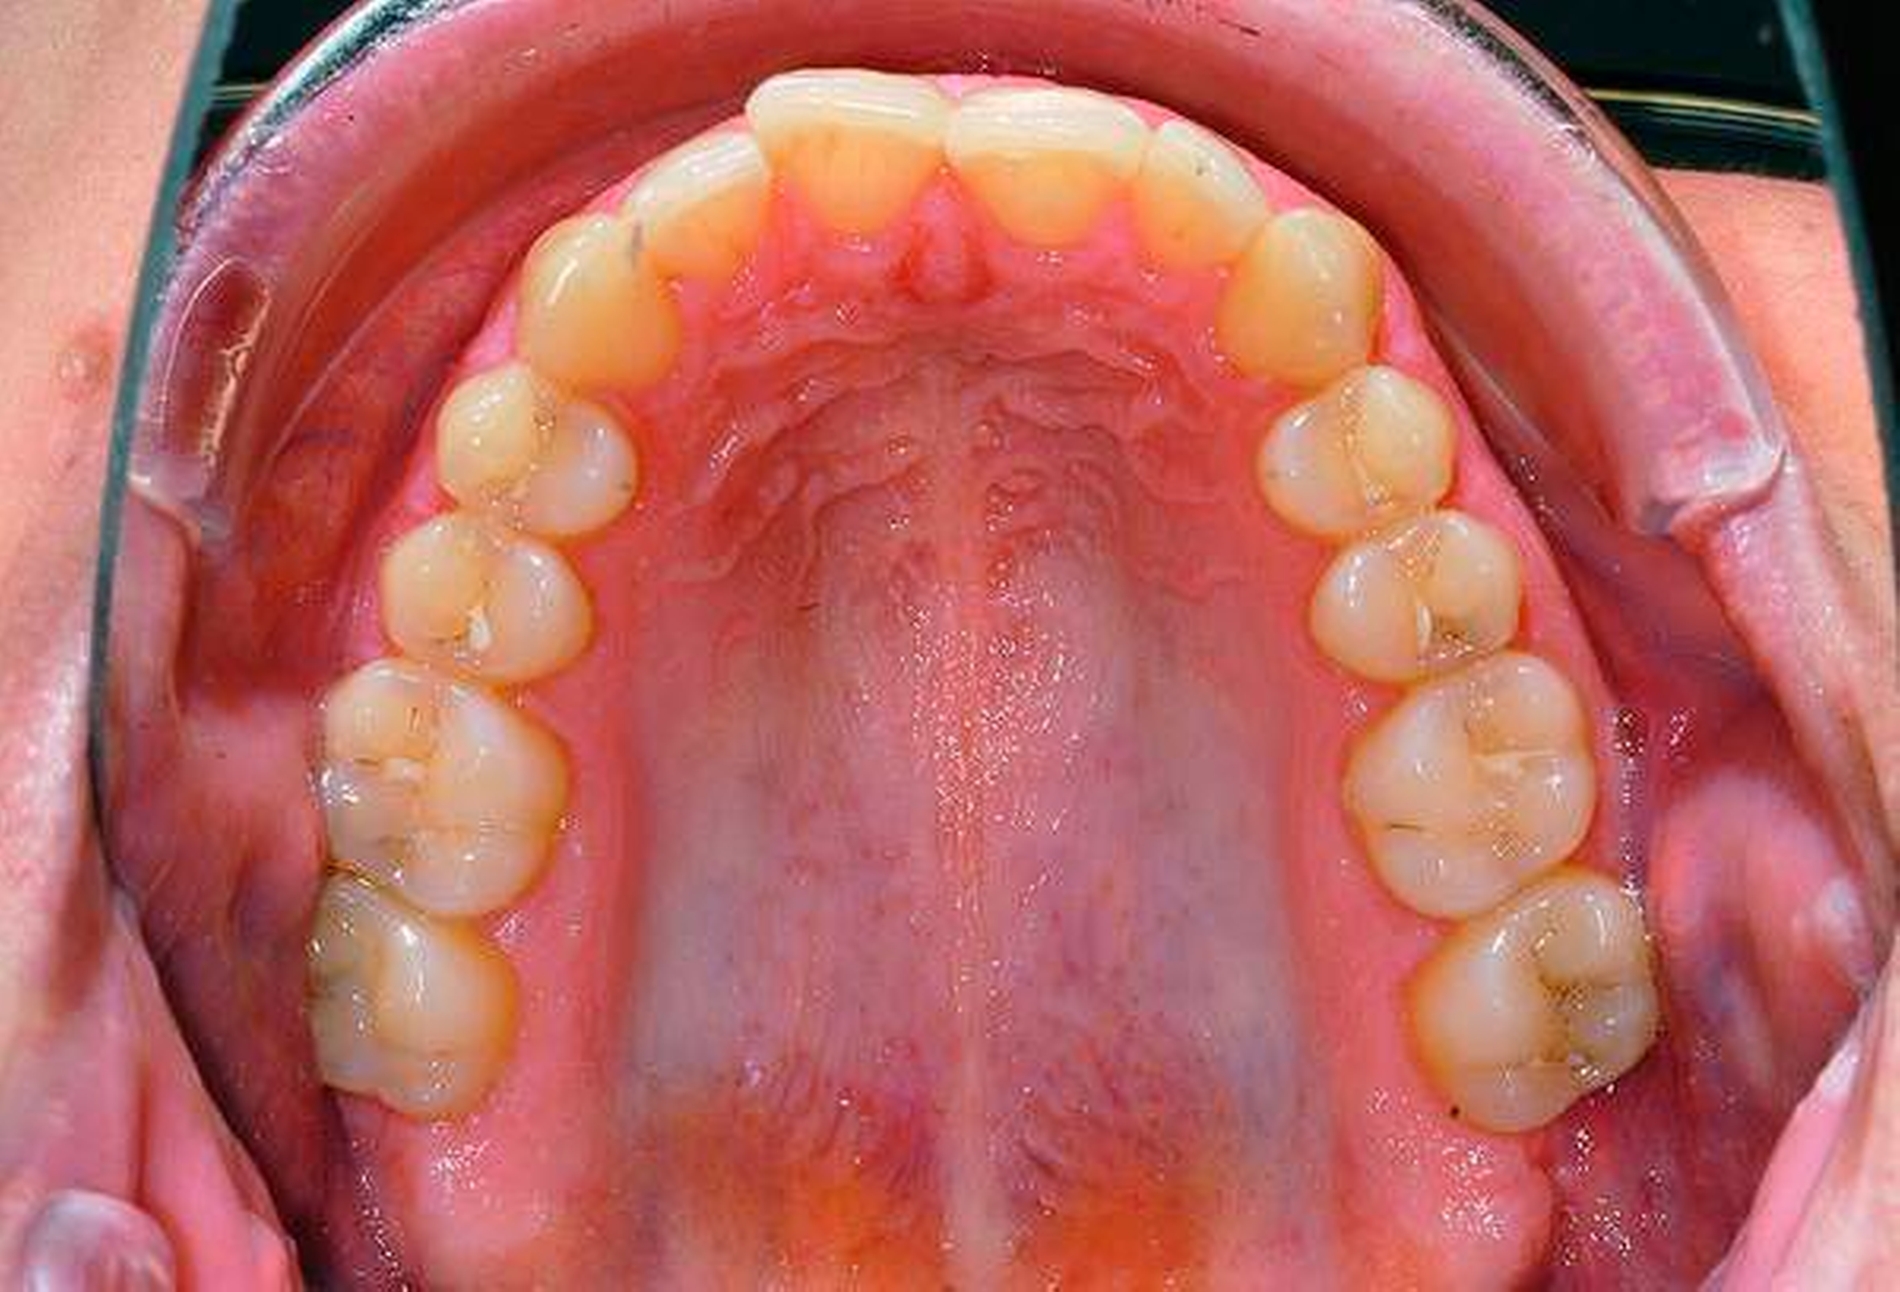

Die Entfernung aller Weisheitszähne wurde schließlich nach einem weiteren frustranen Extraktionsversuch unter Lokalanästhesie in Intubationsnarkose durchgeführt, der postoperative Verlauf gestaltete sich komplikationslos, auffällige Blutungen traten nicht auf (Abbildungen 2 und 3).